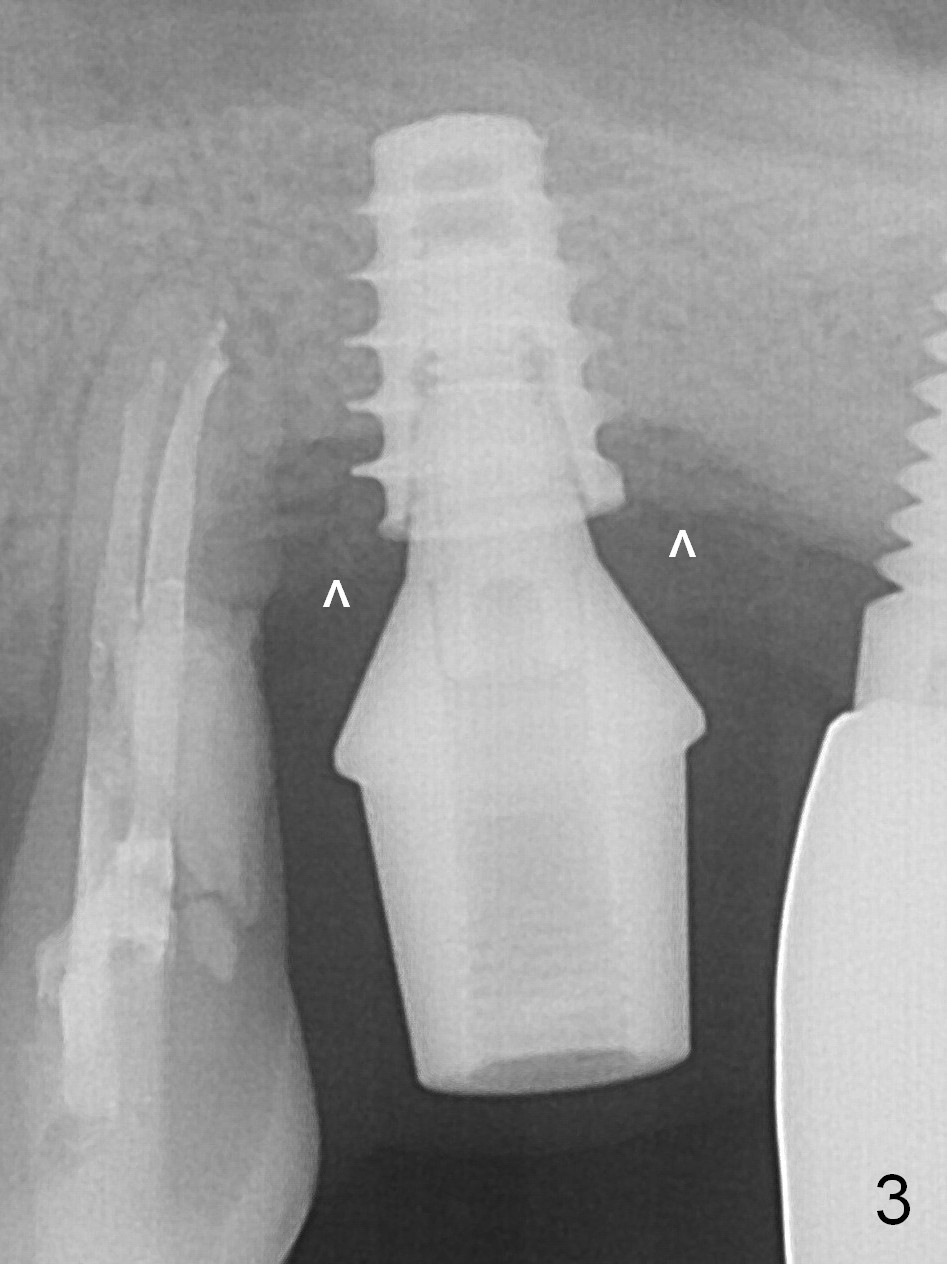

Four months post bone graft, the bone height at #14 is ~ 5 mm (Fig.1). After osteotomy for 4 mm with 4.3 mm Magic Drill (hard bone), Magic Sinus Lifter is used for sinus lift for ~ 8 mm without sinus membrane perforation. Perforation occurs with pulsating hemorrhage after sinus lift with allograft (.5-1 mm, mixed with Metronidazole). Collagen plug is used to repair the perforation before placing a short (5x7 mm) IBS implant with ~ 25 Ncm (Fig.2). After placing a 6.5x5.7(3) mm abutment, allograft is placed around the most coronal exposed implant thread (^). Acrylic is applied over the abutment for wound protection. There is mild nasal hemorrhage for 2 days postop. To prevent and treat sinus membrane perforation, PRF will be routine prepared preop for future cases. New bone forms apically and coronally 4.5 months postop (Fig.3,4 ^). A new temporary crown is fabricated so that it can undergo progressive loading for a few months before final impression. The definitive restoration is delivered 7.5 months postop (Fig.5). The bone density apical to the implant becomes apparently denser nearly 5 months post cementation (Fig.6). The bone density in the crest increases 2 years post cementation (Fig.7 *).